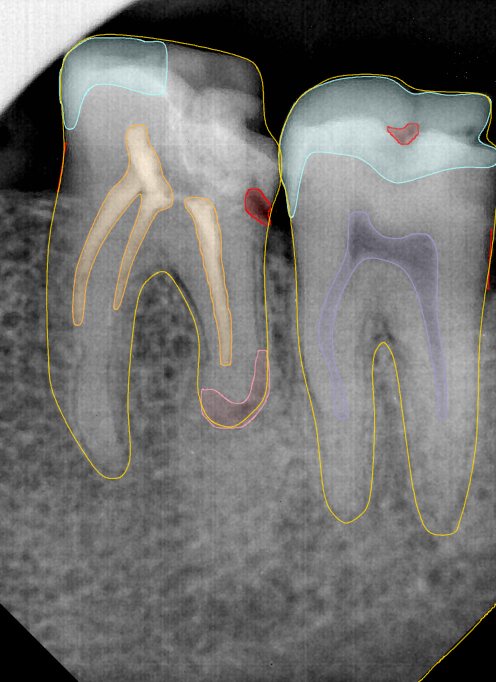

CR/DR 牙齿分割阶段记录

当前进展

- 完成了 CR/DR 牙齿相关分割训练

- 当前结果已经达到阶段预期,但仍有细节问题需要继续处理

相关测试

遇到的问题

- 训练过程中出现过 mask 下移问题

- 部分结果会出现 box 填充异常

- mask 边缘仍然有比较明显的锯齿感

参考